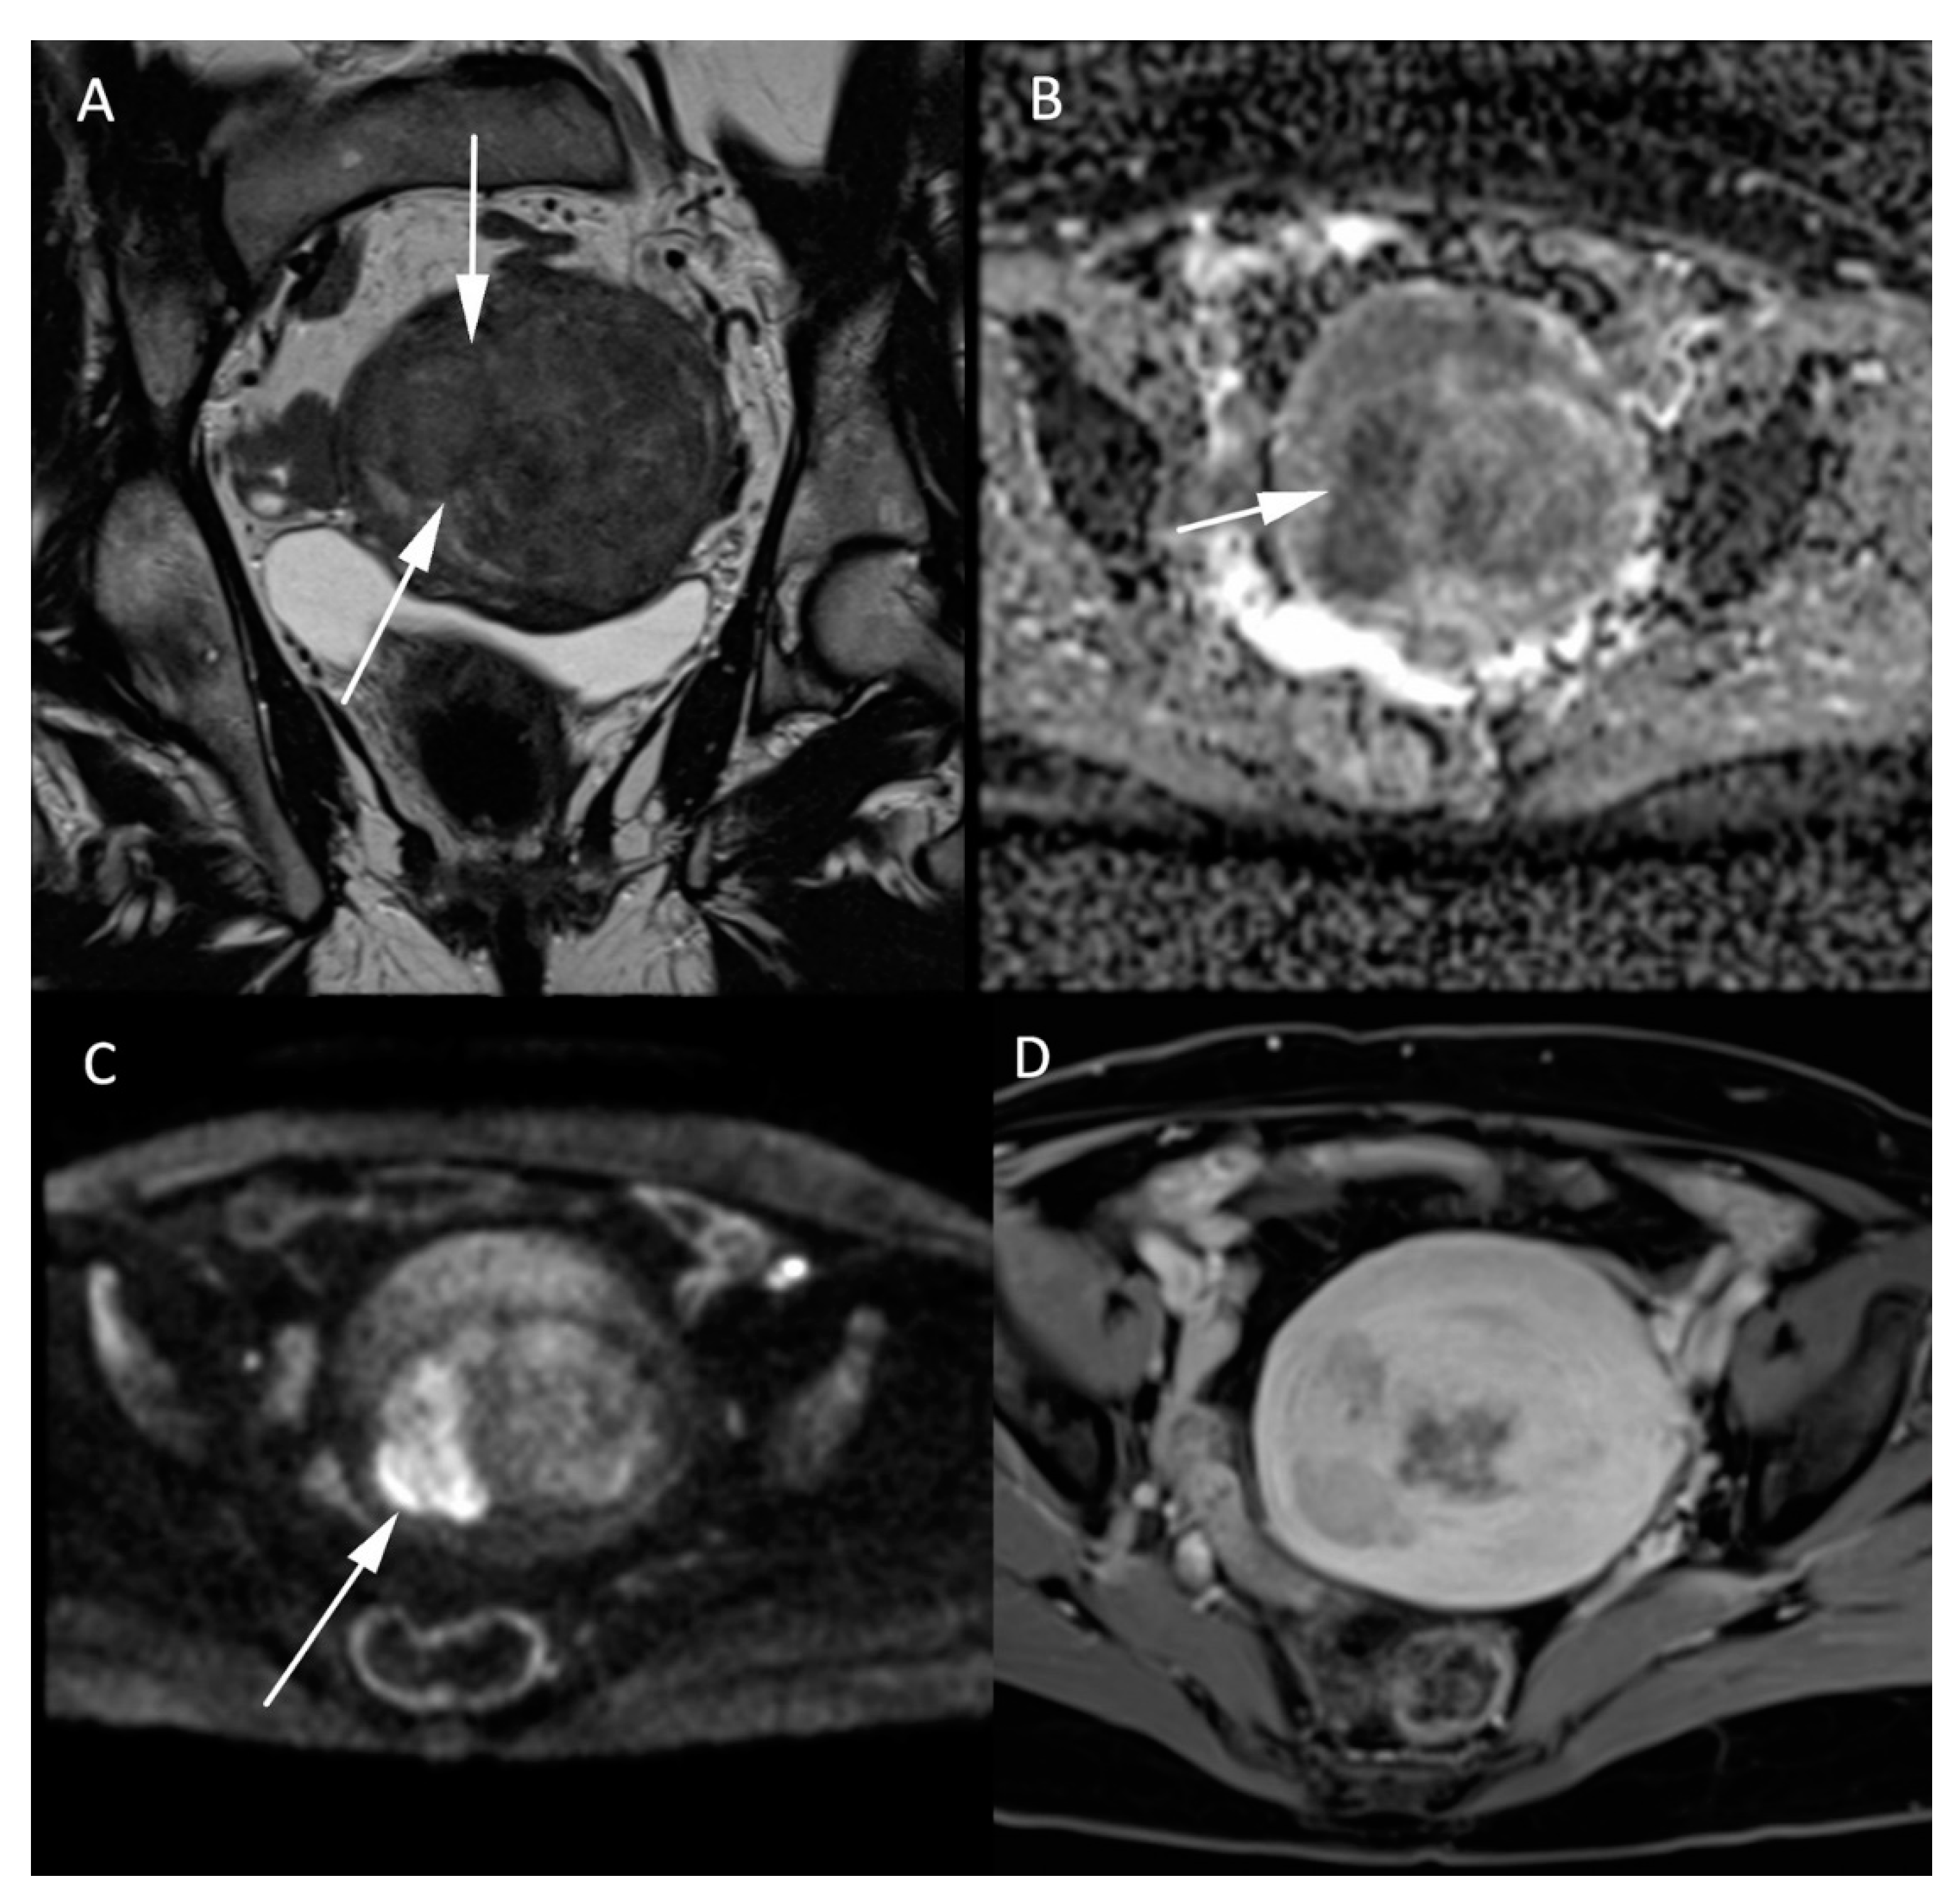

Normal ovaries usually show high SI on both the high b-value sequences and the corresponding ADC maps, corresponding to the so-called “T2 shine-through” effect. DWI is essential for the characterization of a suspicious solid component in heterogeneous complex ovarian masses, identifying solid high cellularity content in malignant ovarian tumors [32], as per the current European Society of Urogenital Radiology (ESUR) recommendations [33]. Illustrative MR images of adenocarcinoma can be found in Figure 5. The coregistration between the high b-value DWI and the morphologic T2W images is very efficient for this purpose. An adnexal lesion can be classified as benign when its solid component is hypointense on both the high b-value DWI and the T2W images (“dark/dark” lesion) [34]. However, DWI alone does not suffice to assess the malignancy of an ovarian tumor, as some benign lesions, such as mature cystic teratomas, endometriomas, or functional hemorrhagic cysts can show an impeded diffusion [16,32,35]. Dynamic contrast-enhanced MRI sequences are essential to further assess the probability of malignancy.

Figure 5.

Histologically proven left ovary adenocarcinoma in a 64-year-old woman. (A) T2W hyperintense heterogeneous left adnexal mass next to the uterus (*). Tissular bilobed left adnexal mass with parts of low (B) ADC values and high (C) b-1000 signal consistent with a diffusion restriction in the lesion (C). Post injection of gadolinium (D) T1W sequence with fat-saturation shows a heterogeneous enhancement (arrow).